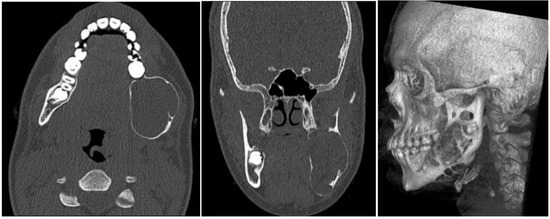

2.1. Case 1